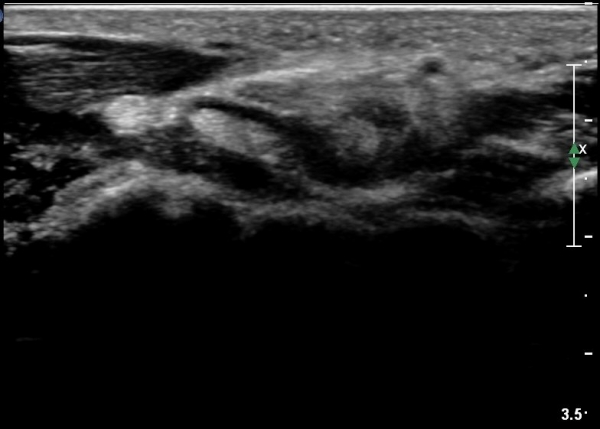

¼ö±Ù°ü ¿øÀ§ºÎ Ⱦ´Ü¸é°Ë»ç¿¡¼­ Á¤Á߽ŰæÀÇ ºÎÁ¾ µî ƯÀÌ ¼Ò°ßÀÌ º¸ÀÌÁö ¾Ê´Â´Ù(»çÁø 3).